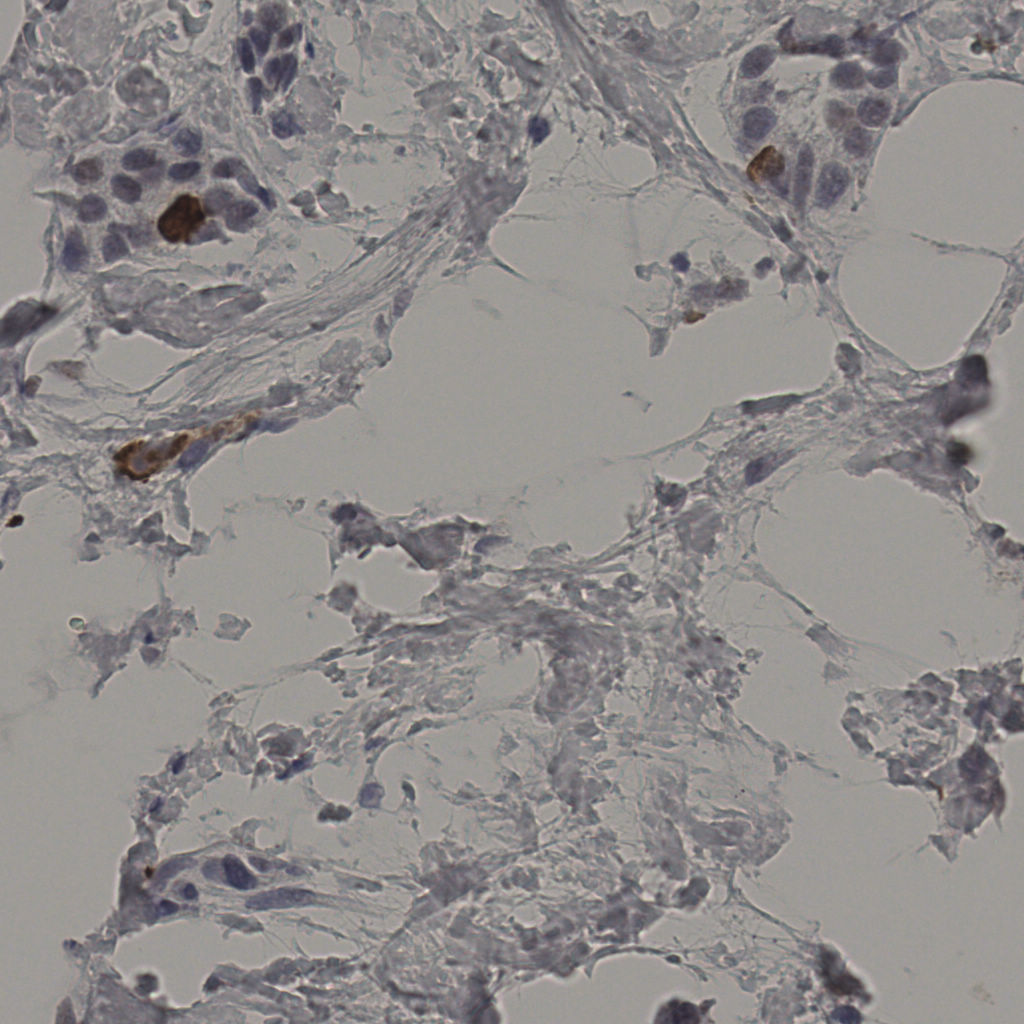

缩略图

标记后

标记前